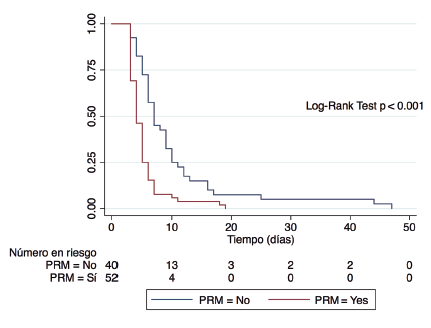

Jorge Lavanderos Fernandez, Virginia Linacre Sandoval, Juan Emilio Cheyre Forestier, Jorge Armijo Herrera, Rafael Prats Manganelly

|

|

|